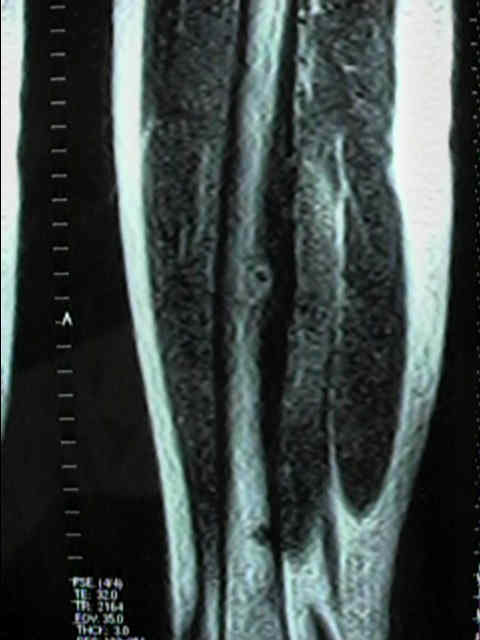

RM:

Generalmente la RM tiene un papel pequeño para el diagnóstico, porque el hueso tiene una señal baja.

A pesar de esto, puede usarse para confirmar el diagnóstico o ayudar a descartar otras lesiones.

Ver imagen